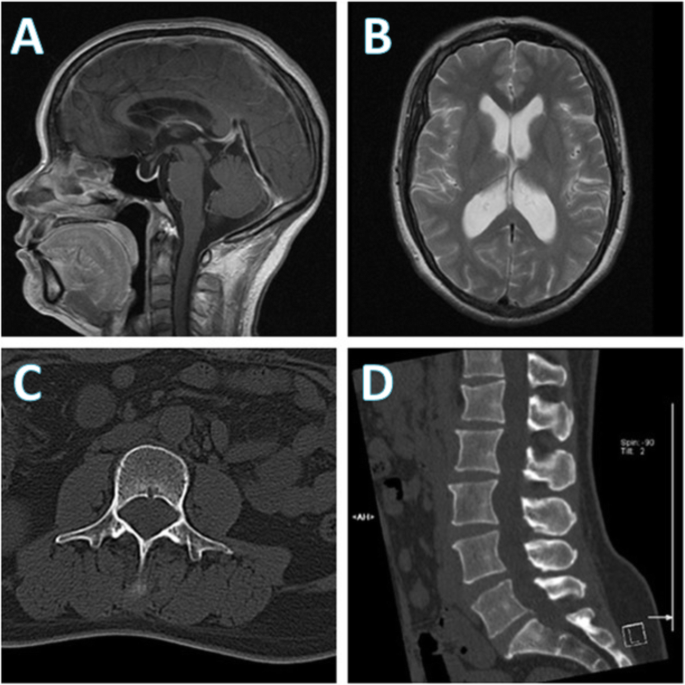

Physical examination revealed a slower light reflex of the left eye, decreased visual acuity of bilateral eyes (more severe on the left) and left nasal hemianopsia. On neurological examination, no neurological localizing signs were observed. Fundus examination showed bilateral papilledema. Brain magnetic resonance imaging (MRI) showed no occupying lesions, only mildly dilated ventricles (Fig. 1a and b). Lumbar puncture (LP) revealed a significantly elevated pressure of 330 mmH2O. Laboratory examination of cerebrospinal fluid (CSF) indicated a normal cell count of 4 × 106/L (normal range 0–8 × 106/L) and a significantly increased protein level of 382.6 mg/dL (normal range 0–43 mg/dL). Given the other negative results of CSF ink stain, blood T-SPOT tuberculosis, and normal computed tomography (CT) scan of the lung, the neurologists excluded intracranial tuberculous and cryptococcal infection. Meningeal carcinomatosis was also not considered due to the slow progression, though CSF cytology was not investigated.

Brain magnetic resonance imaging (MRI) and lumbar computed tomography (CT) performed during the patient’s first admission. a Brain MRI demonstrated mild enlargement of the supratentorial ventricle, b the abnormal sign of vacuolar sella in the right optic-radiation of lateral thalamus, bilateral medial temporal lobes, and the insular lobes. c, d No abnormalities were found in lumbar CT at first; however, a retrospective review of the spinal CT scan (d) showed the evidence of enlarged neural foramina and mild vertebral scalloping which suggested a long-standing intradural tumor such as schwannoma

A diagnosis of cranial venous sinus thrombosis (CVST) was then suspected and contrast-enhanced magnetic resonance venography (CE-MRV) was performed. The examination showed relatively thin transverse sinus on both sides but no obvious evidence of CVST. Considering the possibility of elevated CSF protein caused by extracranial, and not intracranial, tumors, the neurologists planned for lumbar MRI but failed to perform the examination because of a metal intrauterine device (IUD). Instead, a lumbar CT scan was performed, revealing no abnormalities (Fig. 1c and d). Still, evidence supporting secondary ICH was insufficient. Hence, a digital subtraction angiography (DSA) was performed which showed an obvious stenosis localized in the area of the right transverse sinus, and the venous pressure gradient near the stenosis reached 28 mmHg, which confirmed venous sinus stenosis (Fig. 2a and b). She was then diagnosed with IIH and transverse sinus stenosis (TSS).